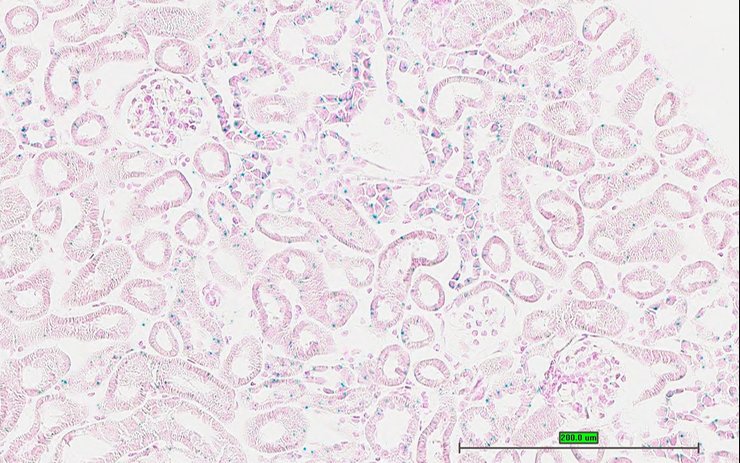

TS28: metanephros Present UC Davis_1884601 kidney

Specimen UC Davis_1884602: postnatal adult; Bcs1ltm1.1(KOMP)Vlcg/Bcs1l+ (more )

TS28: metanephros Present UC Davis_1884602 kidney

Specimen UC Davis_1884603: postnatal adult; Bcs1ltm1.1(KOMP)Vlcg/Bcs1l+ (more )

TS28: metanephros Present UC Davis_1884603 kidney

TS28: metanephros Present UC Davis_1884647 kidney

Specimen UC Davis_1884648: postnatal adult; Bcs1ltm1.1(KOMP)Vlcg/Bcs1l+ (more )

TS28: metanephros Present UC Davis_1884648 kidney

Specimen UC Davis_1884649: postnatal adult; Bcs1ltm1.1(KOMP)Vlcg/Bcs1l+ (more )

TS28: metanephros Present UC Davis_1884649 kidney